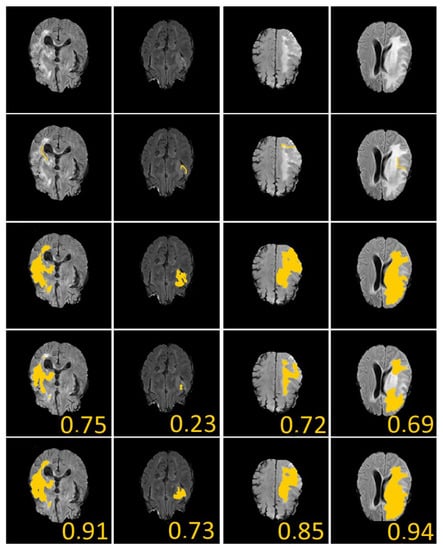

Of course, a large Dice coefficient or a small HD means an accurate segmentation result. Figure 8 shows several numerical example (here, we ramdomly sampled 33% of BRATS labeled dataset). In Figure 8, we give the dice score obtained for U-Net and our proposed algorithm. We can see that our approach clearly gives better results.

Figure 8. Brain Tumor Segmentation (using BRATS dataset [28]). Several results from our method using labeled data on the BRATS dataset [28]. The tumor is underlined in yellow. First row: center slices of input. Second row: initial conditions for our algorithm. Third row: ground-truth labels. Fourth row: results from the supervised U-Nets learning method introduced by Ronnenberger et al. [27]. Fifth row: results from our proposed method. The scores in the bottom of each results denote Dice score.